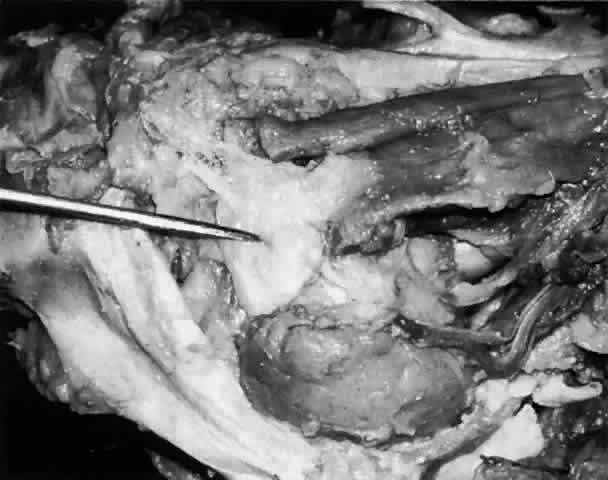

The parenchyma of the gland is made up of small lobules separated by a fine connective tissue network. The lacrimal gland has approximately 12 secretory ducts (Fig. 7), which average 0.66 mm in diameter and 2.31 mm in length.4 Two to five of them originate from the orbital lobe and six to eight from the palpebral lobe. The ductules from the orbital portion of the lacrimal gland pass through the parenchyma of the palpebral lobe before exiting into the superotemporal portion of the conjunctival fornix 4 or 5 mm above the upper border of the tarsus. One or two may open near the lateral canthus.5 Excision of the palpebral lobe may therefore interrupt drainage from the orbital lobe as well.

Fig. 7. Secretory ducts (arrow 1) of the right lacrimal gland (arrow 2) are seen passing to the palpebral conjunctiva (arrow 3). (Courtesy of James Sanderson, MD, Orkan Stasior, MD, and George Stasior, MD)